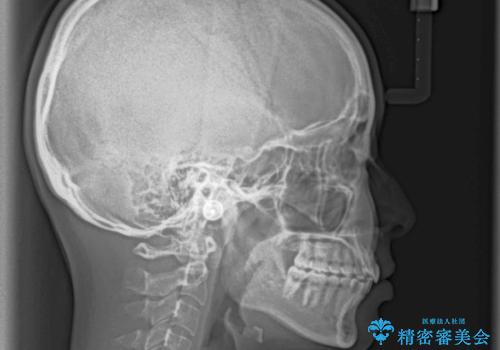

歯列全体の拡大とIPR(歯と歯の間を削る)によってデコボコが解消するようにし、さらにゴムかけを活用して右側の咬み合わせ位置を変えるように設計し、インビザラインにより治療を行うこととしました。

後方移動に際し、上下顎の親知らずは3本とも抜歯することとしました。

結婚式までに前歯を整えたいとのことでしたが、インビザラインでは先に奥歯を移動させてから前歯を動かすため、間に合わない可能性がありました。しかし、結婚式までに期間があったことと、マウスピースをしっかりと装着してくださったことで、十分な歯列に整えることができました。